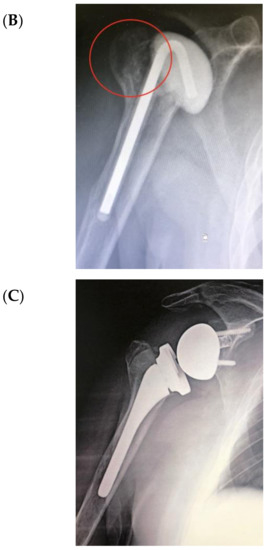

The bone substitute GlassBONE Putty (Noraker, Villeurbanne, France), made of bioactive glass, was routinely employed in revision surgeries requiring bone loss filling in our surgeries. This ceramic is composed of Silicium, Calcium, Sodium and Phosphorous, minerals which are naturally present in the human body; it is in a ready-to-use format and can be injected through the syringe (Figure 1): it may be used both to increase prosthesis-bone interface stability and fill bone defects in PJIS revision surgeries, also contributing to preventing re-infection. In this regard, a peculiar case was reported (Figure 2): infection after percutaneous treatment of a proximal humerus fracture. The pinning removal and the implant of a cement antibiotic spacer were attempted. Finally, an RSA (Equinoxe Shoulder System, Exactech Inc., Bloomington, MN, USA) was implanted with the addiction of bioactive glass to prevent tuberosity defect augmentation and re-infection.

Figure 2.

An infection after percutaneous pinning of a proximal humerus fracture. (A) Preoperative X-ray. (B) The subsequent implanting of a cement antibiotic spacer (red circle underlines bone loss); (C) the final reverse arthroplasty (RSA) with the addition of bioactive glass in the tuberosity defect.